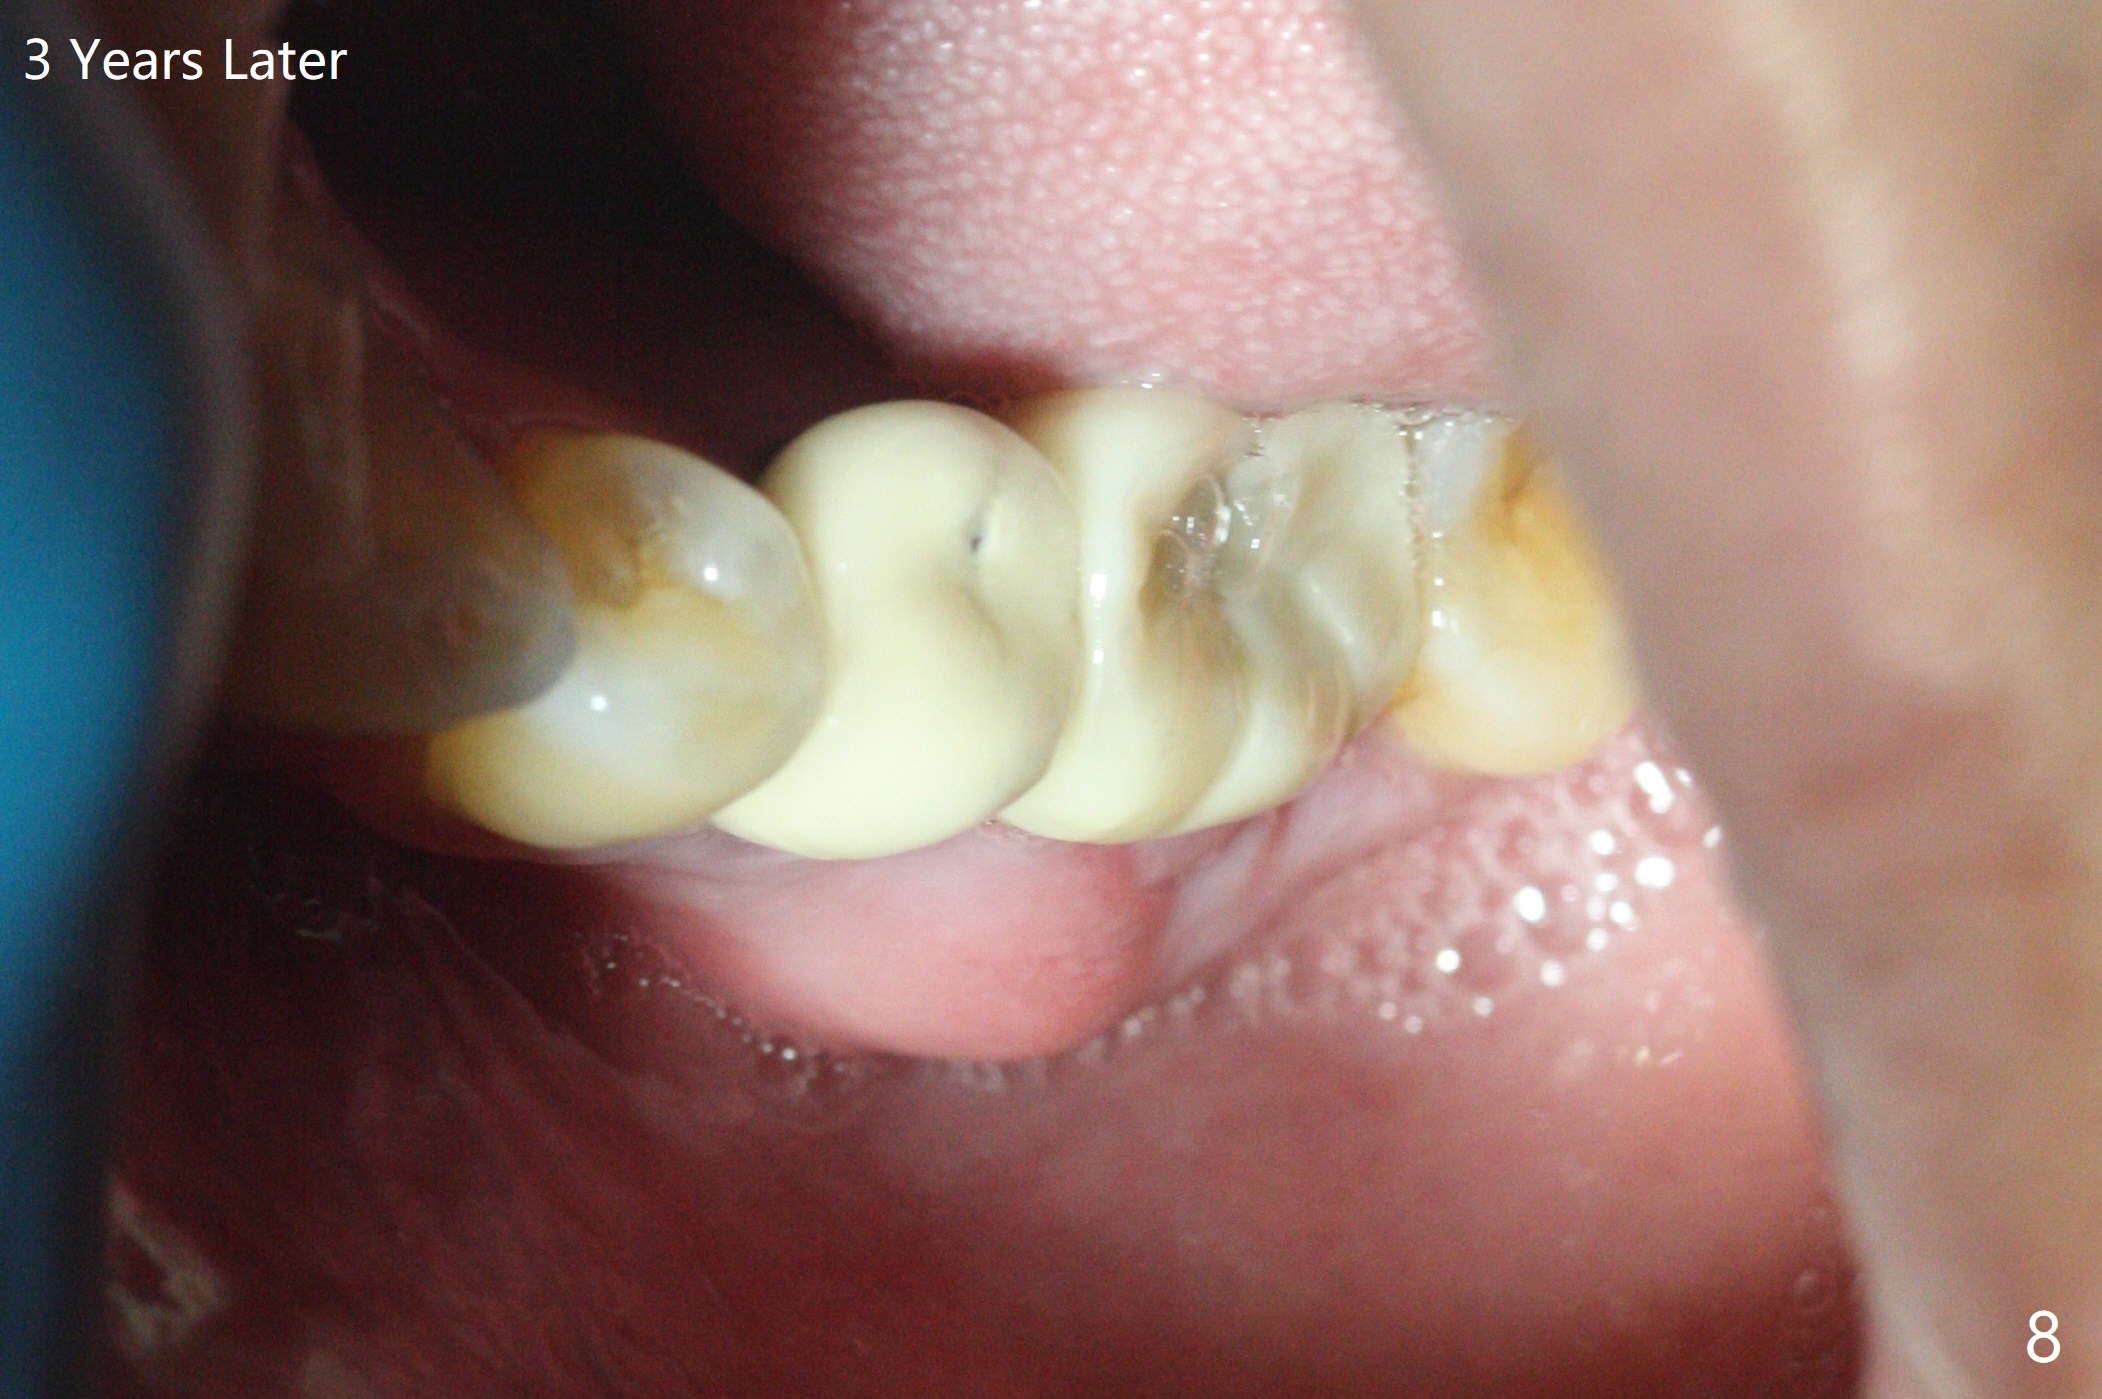

A 54-year-old man has distal (D) root fracture at #19 while the implant at #2 is osteointegrarting (Fig.1,2). Because of the large distal defect (Fig.3, after extraction), osteotomy (red line) will be initiated in the mesial socket (Fig.4, as distal as possible, with the coronal end in the middle of the socket) or the mesial slope of the septum (Fig.5) so that the implant (green) will be supported by the distally displaced septum (Fig.6 arrow). CT taken 8 months later confirms distal root fracture. A 6x11.5 mm or longer implant seems to be appropriate for the site (Fig.7). Three years later there is severe buccal swelling (Fig.8) with vertical mesial and distal root fractures (Fig.9). Although the buccal plate is lost, the septum remains (Fig.10 S), which will provide with blood supply to the bone graft (Fig.11), covered with Bioxclude and 6-month membrane and PSA suture. The bone density in the mesial and distal sockets is higher than that in the septum 8 months post cortical bone graft (Fig.12). In spite of bone graft, the buccolingual width reduces by almost 4 mm 8 months post extraction (Fig.3,4). In spite of bone graft, the buccolingual width reduces by almost 4 mm in 8 months post extraction (Fig.3,4). A 5x11.5 mm implant will be placed (Fig.15).